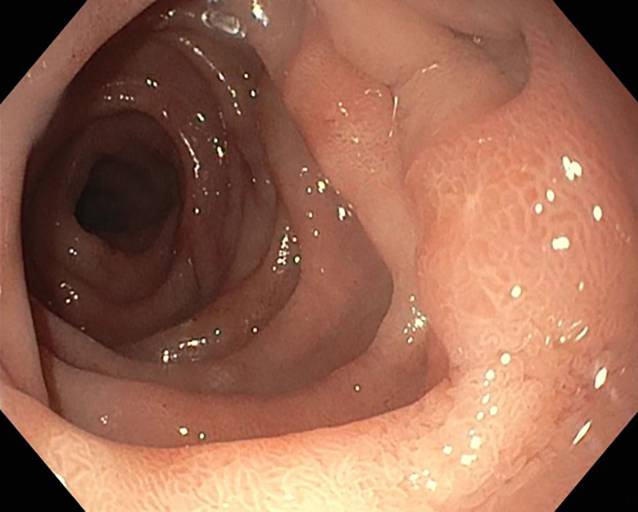

In der ersten endoskopischen Kontrolle nach 3 Tagen zeigten sich regelhafte, reizlose Nahtverhältnisse mit leichtem Fibrinbelag auf der Naht ohne weitere Entzündungszeichen und ohne Defekt bei guten Durchblutungsverhältnissen. Das initiale perifokale Ödem war rückläufig. Die dOFD war nicht disloziert und lag mit dem Drainageelement im Duodenum. Es wurde eine neue dOFD problemlos endoskopisch platziert und die präemptive Therapie noch für eine zweite Periode fortgeführt (Abb. 4).

Abb. 4

Perforationsdefekt (P) am 4. postoperativen Tag, Wechsel der Drainage mit Inspektion der inneren Wunde. Man sieht keinerlei gallige Imbibierung der Wunde, das gallige Sekret wurde komplett abgesaugt. Die Perforationsstelle stellt sich reizlos mit einem minimalen Fibrinbelag dar, kein Defekt nachweisbar